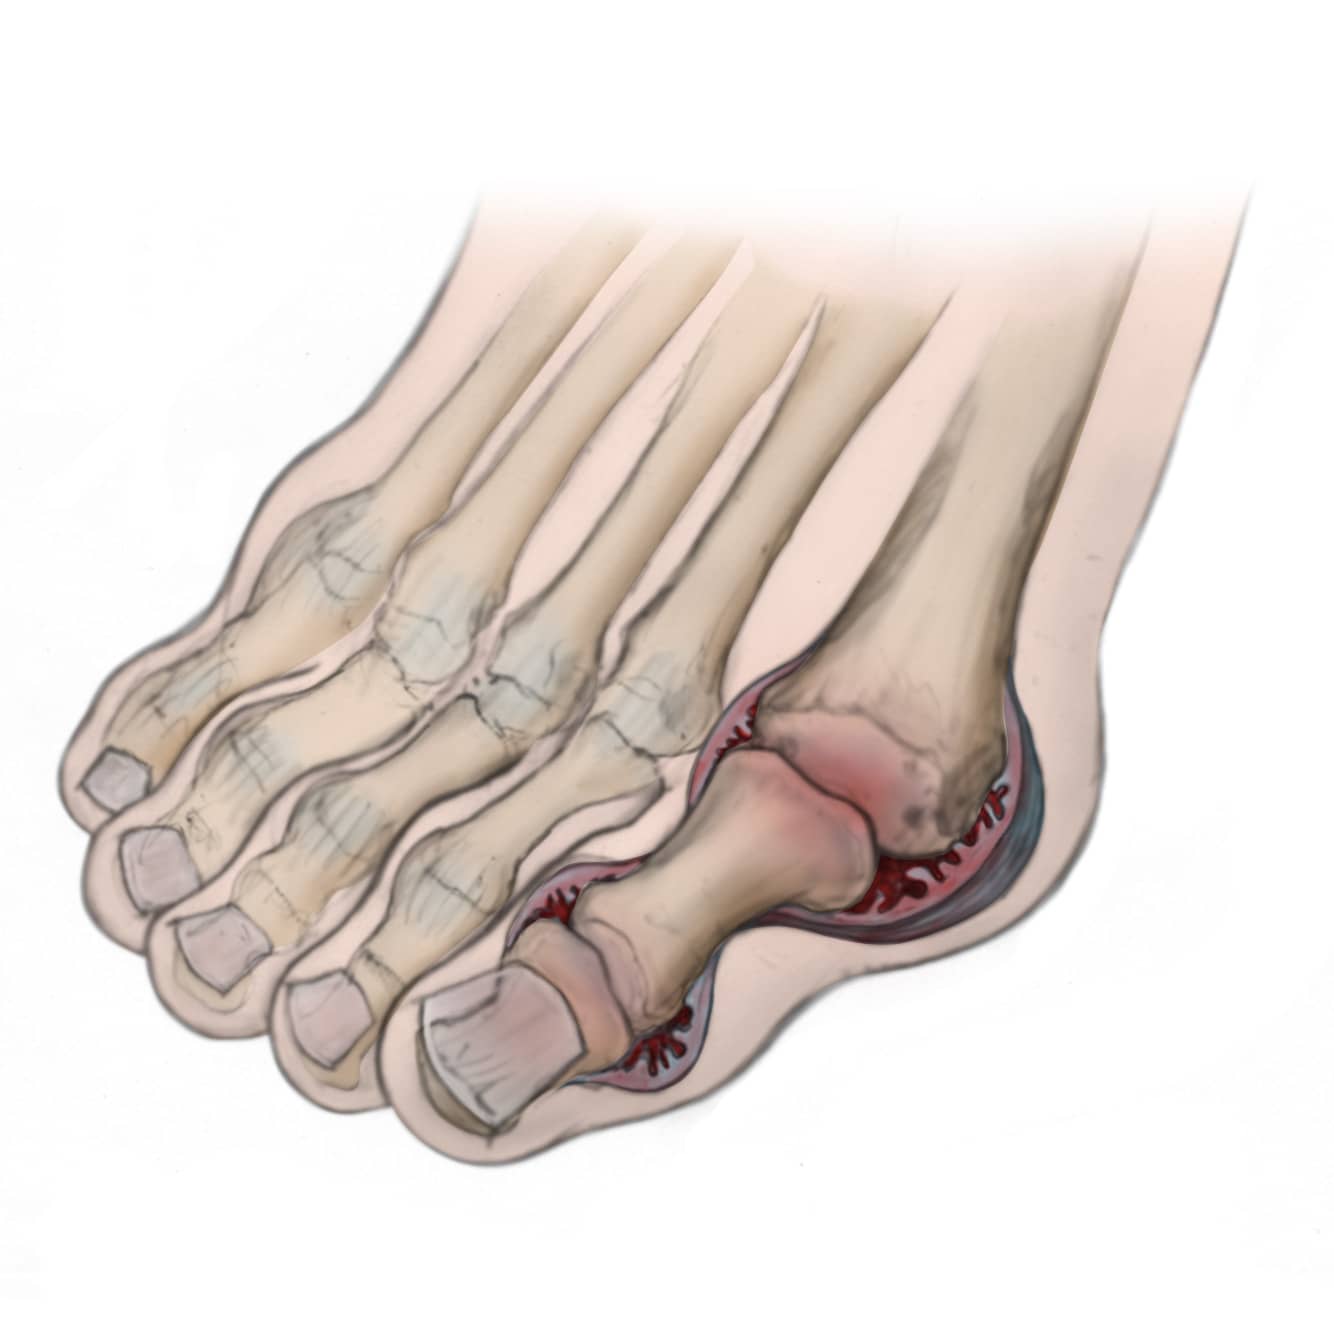

The joints of your body are covered with a lining — called synovium — that lubricates the joint and makes it easier to move. Rheumatoid arthritis causes an overactivity of this lining. It swells and becomes inflamed, damaging the cartilage and destroying the joint, as well as the ligaments and other tissues that support it.

Weakened ligaments can cause joint deformities — such as claw toe or hammer toe. Softening of the bone (osteopenia) can result in stress fractures and collapse of bone.

With RA, the ligaments that support the midfoot become weakened and the arch collapses.

- With loss of the arch, the foot commonly collapses and the front of the foot points outward.

- RA also damages the cartilage, causing arthritic pain that is present with or without shoes.

- Over time, the shape of the foot can change because the structures that support it degenerate. This can create a large bony prominence (bump) on the arch. All of these changes in the shape of the foot can make it very difficult to wear shoes.

Forefoot (Toes and Ball of the Foot)

The changes that occur to the front of the foot are unique to patients with RA. These problems include:

Although each individual deformity is common, it is the combination of deformities that compounds the problem.

- The bunion is typically severe, and the big toe commonly crosses over the second toe.

- There can also be very painful bumps on the ball of the foot, creating calluses. The bumps develop when bones in the middle of the foot (midfoot) are pushed down from joint dislocations in the toes. The dislocations of the lesser toes (toes 2 through 5) cause them to become very prominent on the top of the foot. This creates claw toes and makes it very difficult to wear shoes. In severe situations, ulcers can form from the abnormal pressure.